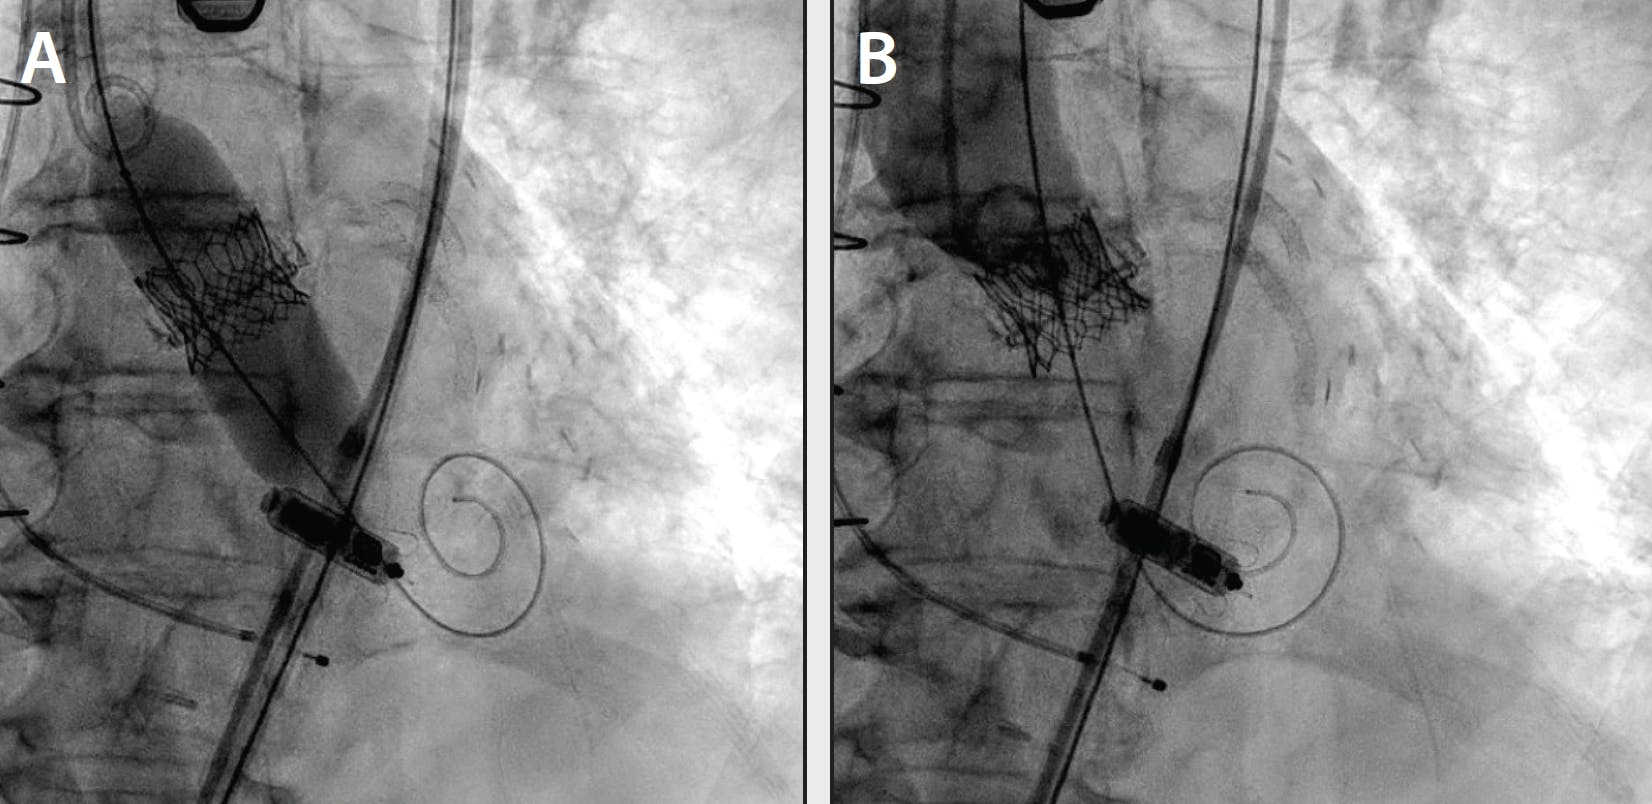

After BASILICA, TAVR was performed with a 20-mm Sapien 3 Ultra Resilia valve (Edwards Lifesciences). The valve was implanted slightly deeper to mitigate the risk of skirt obstruction and was postdilated with a 21-mm True balloon (BD Interventional) to optimize expansion. Final angiography demonstrated unobstructed flow in both coronary arteries. The final invasive transvalvular gradient was 4 mm Hg (Figure 4).

Figure 4. Valve postdilation (A); limited angiography after valve deployment (B).

The patient’s postprocedural echocardiogram demonstrated a mean gradient of 8 mm Hg without paravalvular leak. She was discharged uneventfully.